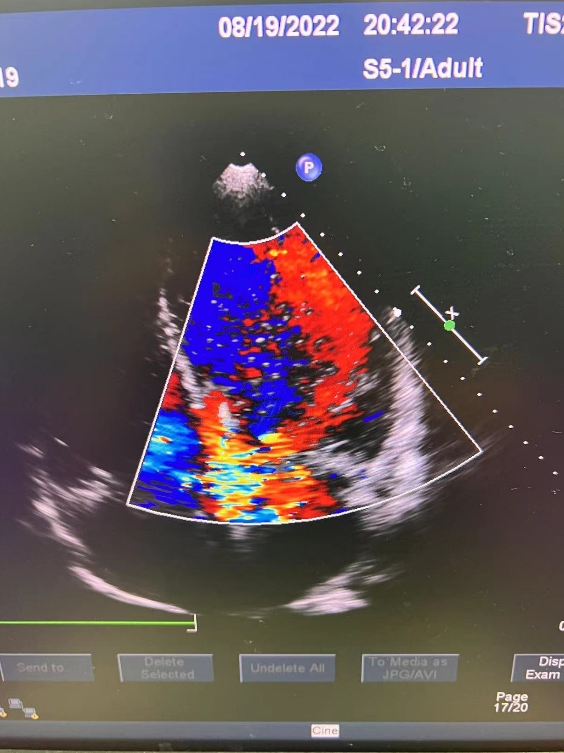

D-Omniheart植入后的心动超声图